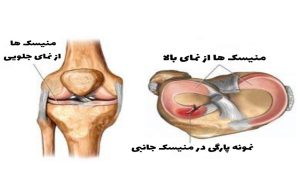

انواع پارگی منیسک

دو نوع مختلف پارگی منیسک وجود دارد:

- پارگی حاد – معمولاً نتیجه یک ضربه یا آسیب ورزشی (ورزشی هایی مانند تنیس، آهسته دویدن، فوتبال، …) است. پارگی های حاد اشکال مختلفی دارند (افقی، عمودی، شعاعی، مایل و پیچیده). اگر آنها به مدیریت محافظه کارانه پاسخ ندهند، ممکن است درمان جراحی انجام شود.

- پارگیهای مزمن – این پارگیها اغلب در افراد مسن اتفاق میافتد و پارگیهای دژنراتیو منیسک هستند که پس از حداقل ضربه یا فشار وارده به زانو ایجاد میشوند. آنها بیشتر با فیزیوتراپی و داروهای ضد التهاب درمان می شوند.

اشکال مختلفی از پارگیهای منیسک وجود دارد، بسته به شکل و محل آنها وقتی در اسکن انجام شده توسط دستگاه تصویربرداری (MRI) دیده میشود.

انواع مختلفی از اشکال پارگی مینیسک زانو وجود دارد که از مهم ترین آنها می توان به:

- پارگی دسته سطلی منیسک ( باکت هندل ) : نزدیک به ۱۰ درصد از پارگی های منیسک در این دسته قرار می گیرند. حرکت طبیعی زانو معمولا غیرممکن است زیرا قسمت پاره شده منیسک باعث قفل شدن زانو می شود.

- پارگی شعاعی منیسک : این یکی از رایج ترین انواع پارگی است. حدود ۲۸ درصد از تمام پارگی های منیسک داخلی در این دسته قرار می گیرند. این پارگیها هم بر روی استخوان درشت نی و هم بر محور بلند رشتههای منیسک عمود میشوند. این بدان معنی است که آنها می توانند با ایجاد اختلال در ساختاری که به توزیع وزن در زانو کمک می کند، فشار بیشتری را بر روی مفصل وارد کنند. این پارگی از لبه داخلی منیسک شروع می شود و تا کپسول ادامه می یابد و در قسمت میانی منیسک ایجاد می شود. پارگی شعاعی منیسک جانبی ، اغلب همراه با پارگی رباط صلیبی-قدامی دیده می شود. این نوع پارگی در قسمت بدون رگ منیسک رخ میدهد که خونرسانی خوبی ندارد؛ بنابراین توانایی بسیار کمی برای ترمیم خودش دارد. به همین علت پارگی شعاعی منیسک اغلب اوقات نیاز به مداخله پزشکی و جراحی دارد.